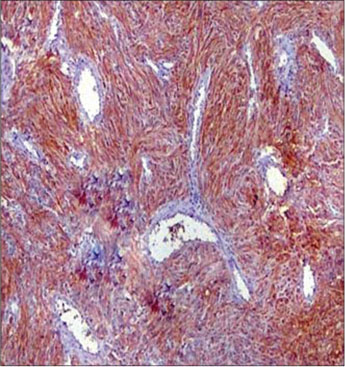

A total of 90 mesenchymal tumors of the GIT and pancreas diagnosed in SKIMS from January 2010 to December 2016 were reclassified on the basis of morphologic features and IHC into 77 (85.6%) cases of GIST and the remaining 13 (14.4%) cases as other mesenchymal tumors. The mesenchymal tumors included five cases of inflammatory myofibroblastic tumors, two cases of leiomyoma, four cases were sarcomas, one case was poorly differentiated carcinoma, and one was desmoid tumor. C-KIT positivity was seen in 72 (93.5%) cases and DOG 1 was positive in 77 (100%) cases [Figures 1], [2], [3], [4]. However, the correlation between DOG1 and CKIT was found to be statistically insignificant (P = 0.23). There was no significant association between DOG 1 expression and various histopathological parameters in the studied cases. Clinicopathological variables have been enumerated in [Table 1].

| Figure 2 Microscopic view of gastrointestinal stromal tumor